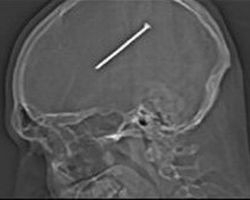

Житель пригорода Чикаго случайно забил себе в череп восьмисантиметровый гвоздь, однако врачам удалось успешно извлечь его из самого центра мозга мужчины, и сейчас он быстро идет на поправку, передает ВВС.

34-летний Данте Отулло находился в своей мастерской, когда пистолет для забивания гвоздей случайно сработал рядом с его головой. Однако рабочий даже не понял, что ему в череп вошел гвоздь, пока на следующий день не почувствовал легкое недомогание и тошноту.

По словам врача, осматривавшего Отулло, гвоздь прошел в нескольких миллиметрах от отдела мозга, отвечающего за двигательные функции.

Сначала Отулло думал, что пистолет для забивания гвоздей просто ударил его по голове наконечником, однако позже понял, что при контакте со лбом сенсор распознал гладкую поверхность и пистолет автоматически выстрелил.

Несмотря на то, что на черепе много нервных окончаний, которые чувствуют боль, в самом мозгу они отсутствуют.

Представитель больницы Майк Маджио сообщил, что фрагмент черепа, вырезанный в ходе операции, пришлось заменить титановой пластиной, так как была вероятность заражения поврежденного участка.